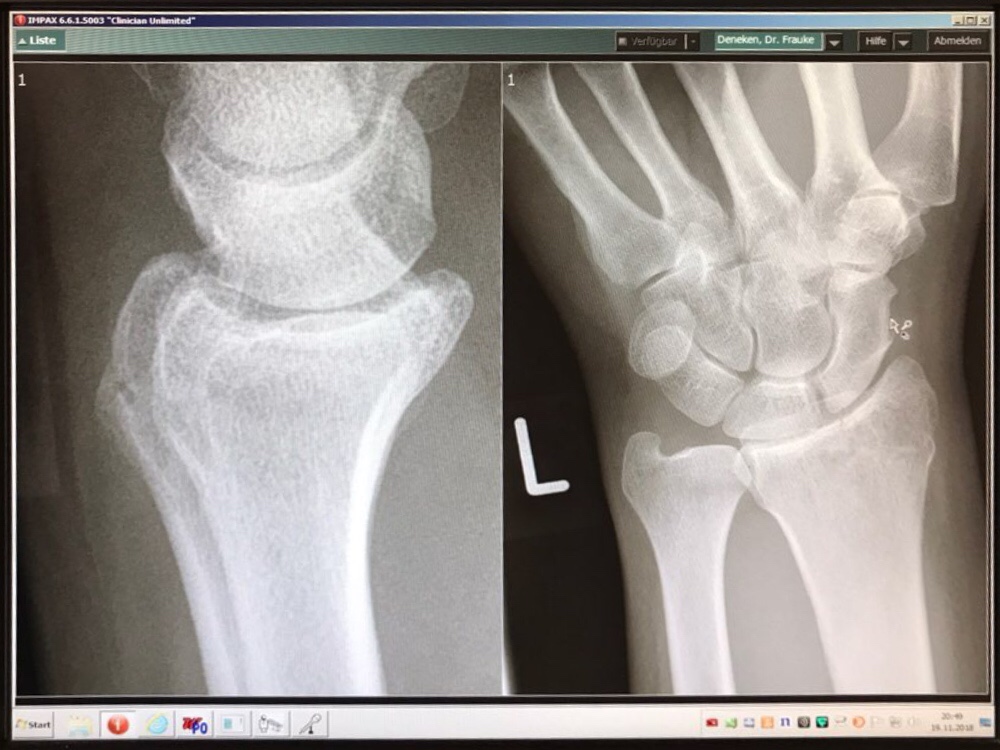

Ein Sturz auf dem Heimweg von der Arbeit hat leider zur Folge, dass das Rad seit Ende November 2018 ungenutzt in der Garage steht.